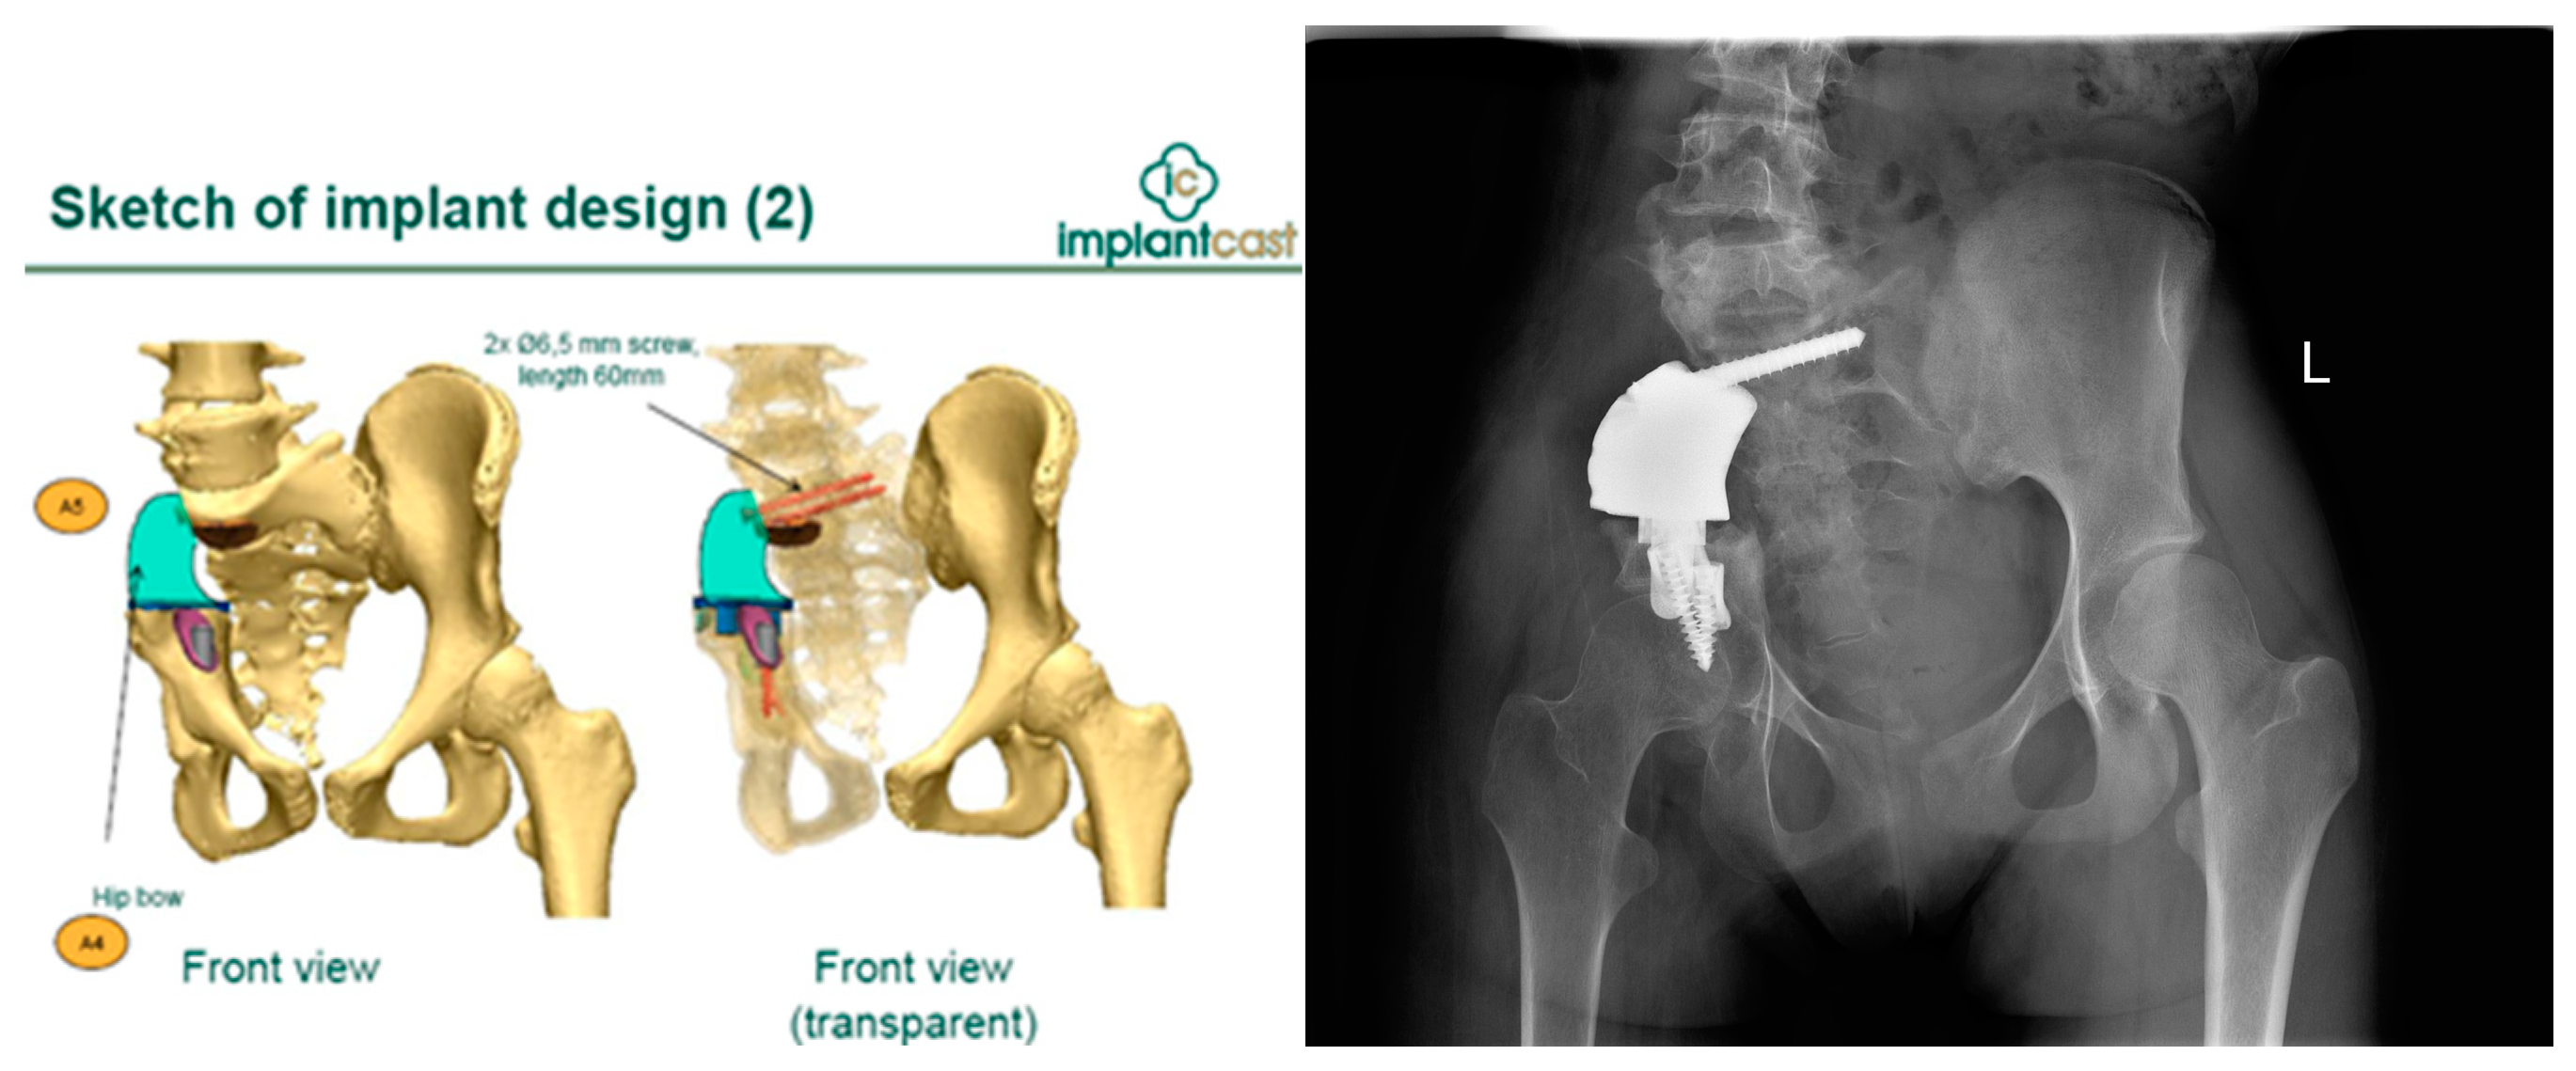

3.3.1. Pelvis Osteosarcoma